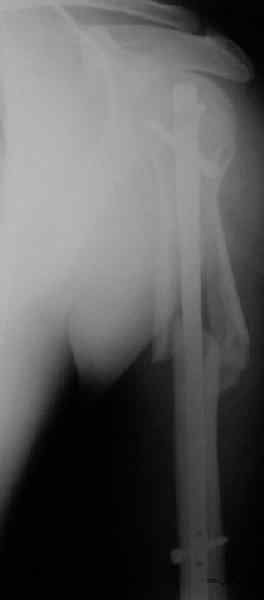

Попытка закрыто изменить положение не удалась. Передним доступом

сделали открытую репозицию, гленоид без особенностей. Временно

фиксировали спицами и остроконечным костедержателем. Фиксировали

гвоздем T2 PHN (Stryker). Для профилактики вывихов после введения

проксимальных винтов ротировали дистальный отдел кнаружи на 30

градусов как аналог остеотомии по Weber. Снимки в приложении.

Attempt of closed reduction failed. Open reduction via anterior

approach. The head was temporarily fixed by wires and sharp clamps.

Fixation by a nail - T2 PHN (Stryker). The distal fragment has been

rotated 30 degrees externally after proximal locking for dislocation

prevention as "virtual" Weber osteotomy. Images attached.